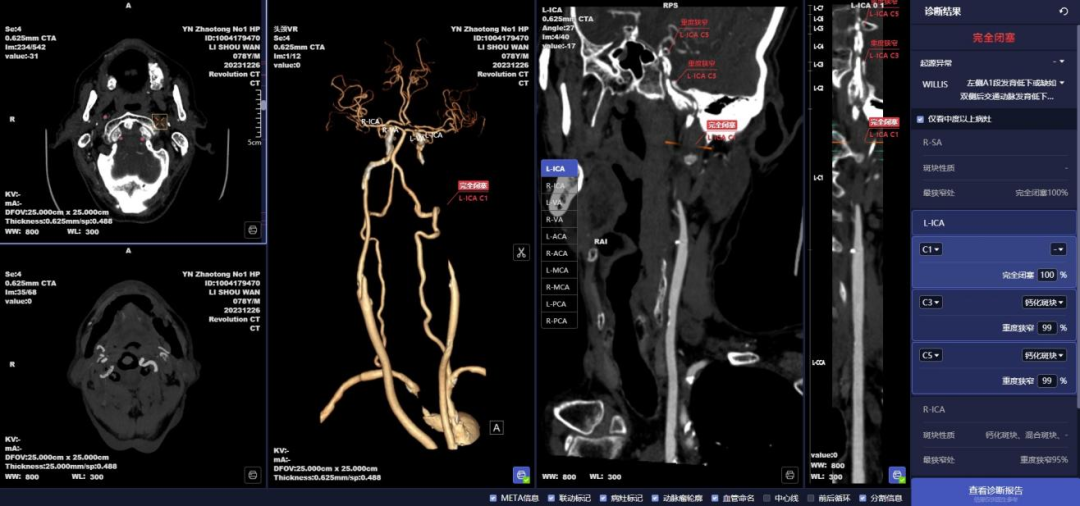

昭通市第一人民医院放射科简介: